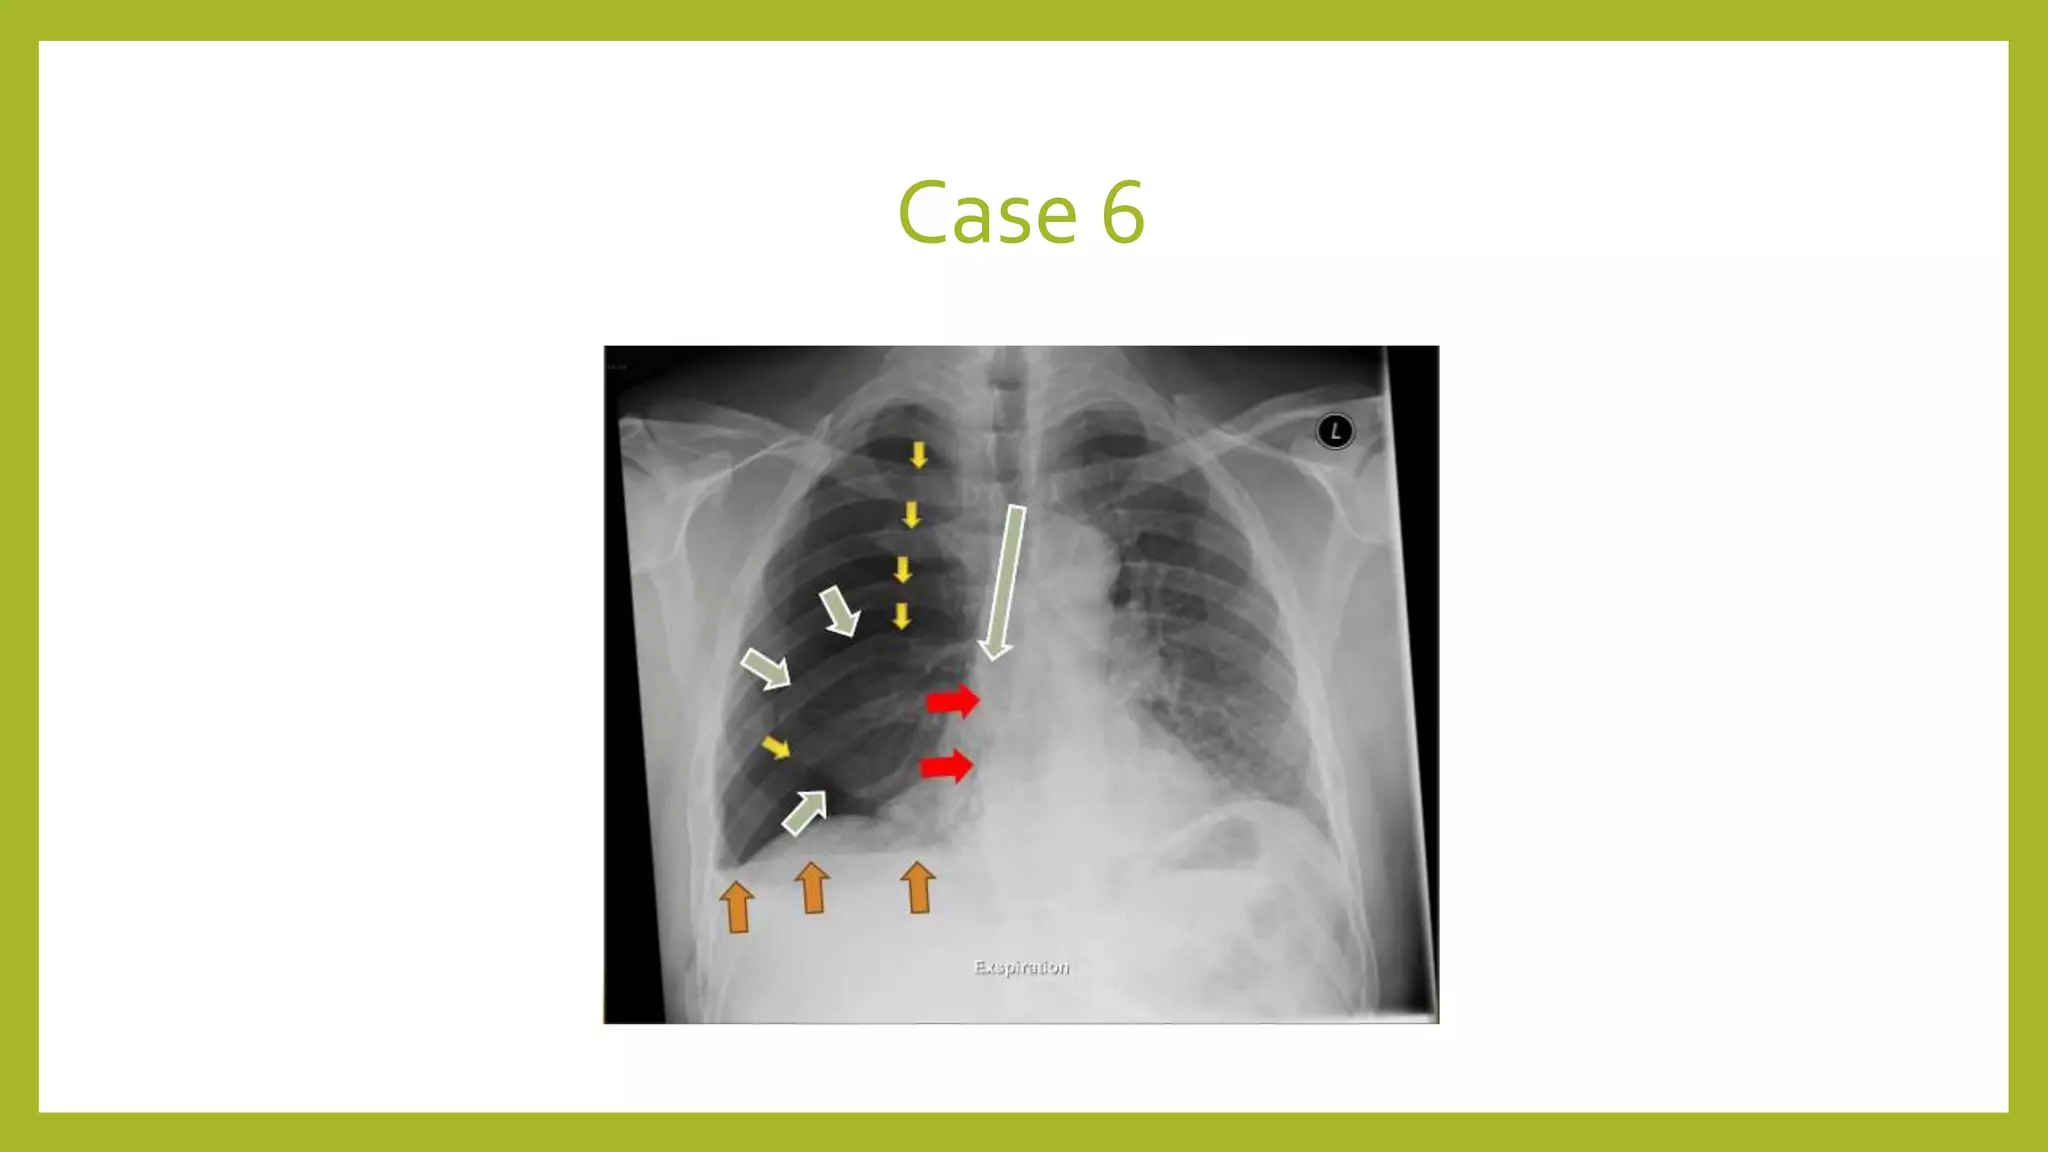

The document provides guidance on approaching and interpreting chest x-rays (CXR). It outlines steps to check the name, date and quality of the film, systematically scan the CXR looking for abnormalities, and determine if the lungs appear too white or black. Specific signs are described to help localize abnormalities, including the cardiac silhouette sign and pleural effusion signs. Examples are given of respiratory distress syndrome, tetralogy of fallot, transposition of great arteries, and total anomalous pulmonary venous return. The take home message is to summarize positive findings, compare to prior CXRs if available, and confirm findings with a radiologist.